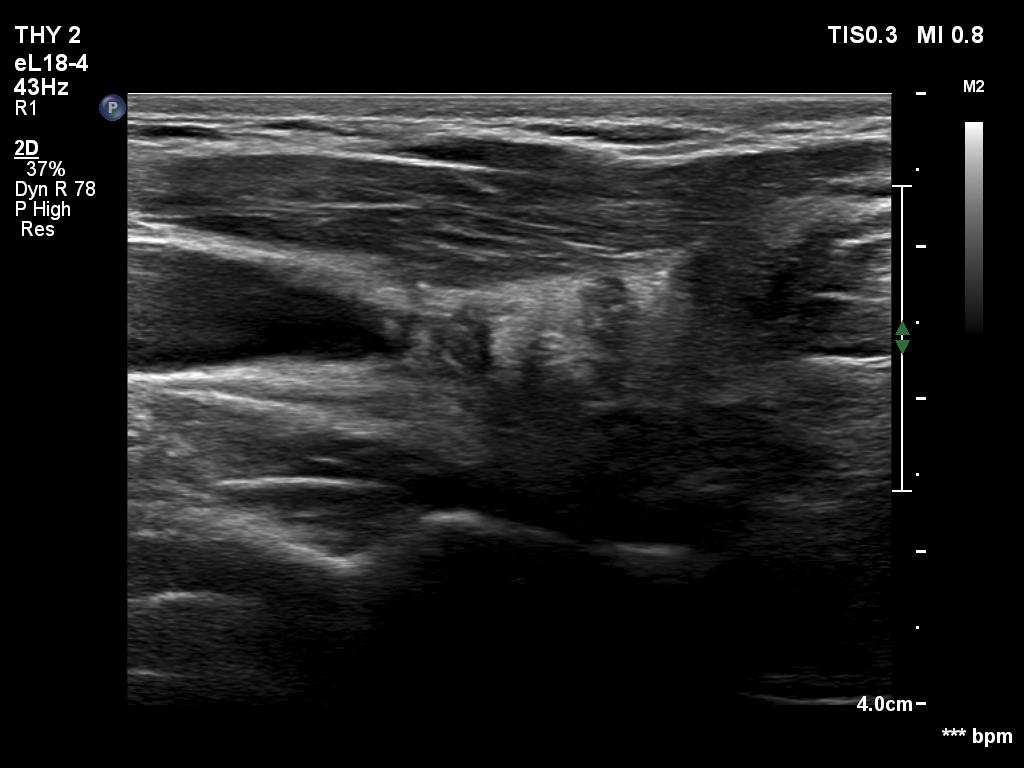

First examination (1st to third rows of images):

Ultrasonography revealed a hypoechogenic nodule in the ventromedial part of the left lobe. The nodule had irregular borders, contained microcalcifications and displayed perinodular and irregular intranodular blood flow.

Histopathology disclosed an embryonal-type follicular adenoma in the left lobe. Almost the entire lobe was consisted of the adenoma. There were within the nodule large fields of lymphocytic infiltration. In the middle portion of the nodule a papillary carcinoma was found with a maximal diameter of 15 mm with metastasis to 3 of the removed 9 lymph nodes in the left side of the neck.

Comments.

It is evident that the cytological material was gained not from the papillary carcinoma but from the adenoma.

It is hard to decide which portion of the lesion corresponded to the carcinoma